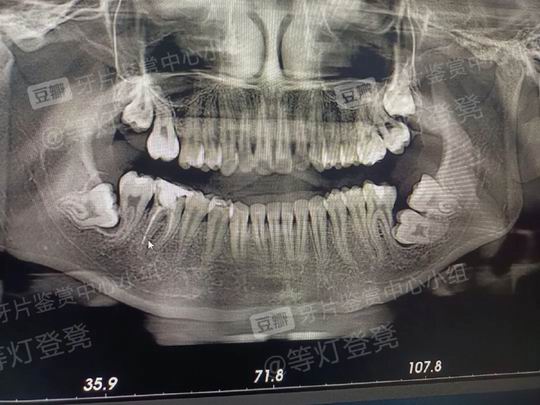

智齿得拔了啊,神奇你居然一颗大牙没长出来

uu 们,我从小在牙科诊所治疗无数次

之前去大的牙科诊所拍过片子,医生也没有什么讶异的反应,就按部就班的治疗。

今天因为牙龈发炎到当地诊所拍了片子,刚拍好走出来看到总共六七个医生围着我的牙片惊叹我的牙齿太特别了😢😢😢

年纪最大的那个医生说这个片子真的很有价值啊,其他医生都非常激动用手机围着我的牙片疯狂拍照和同事分享😭

还有一位女牙医说:“你上辈子肯定干了不少大事”

呜呜呜呜确实太奇怪了,表面看上去没啥特别甚至同学们还以为我牙齿很好很齐,但是把看牙当家常便饭的我深知我的牙齿问题很大。

我想知道我这些牙齿又要花费多少 money😭